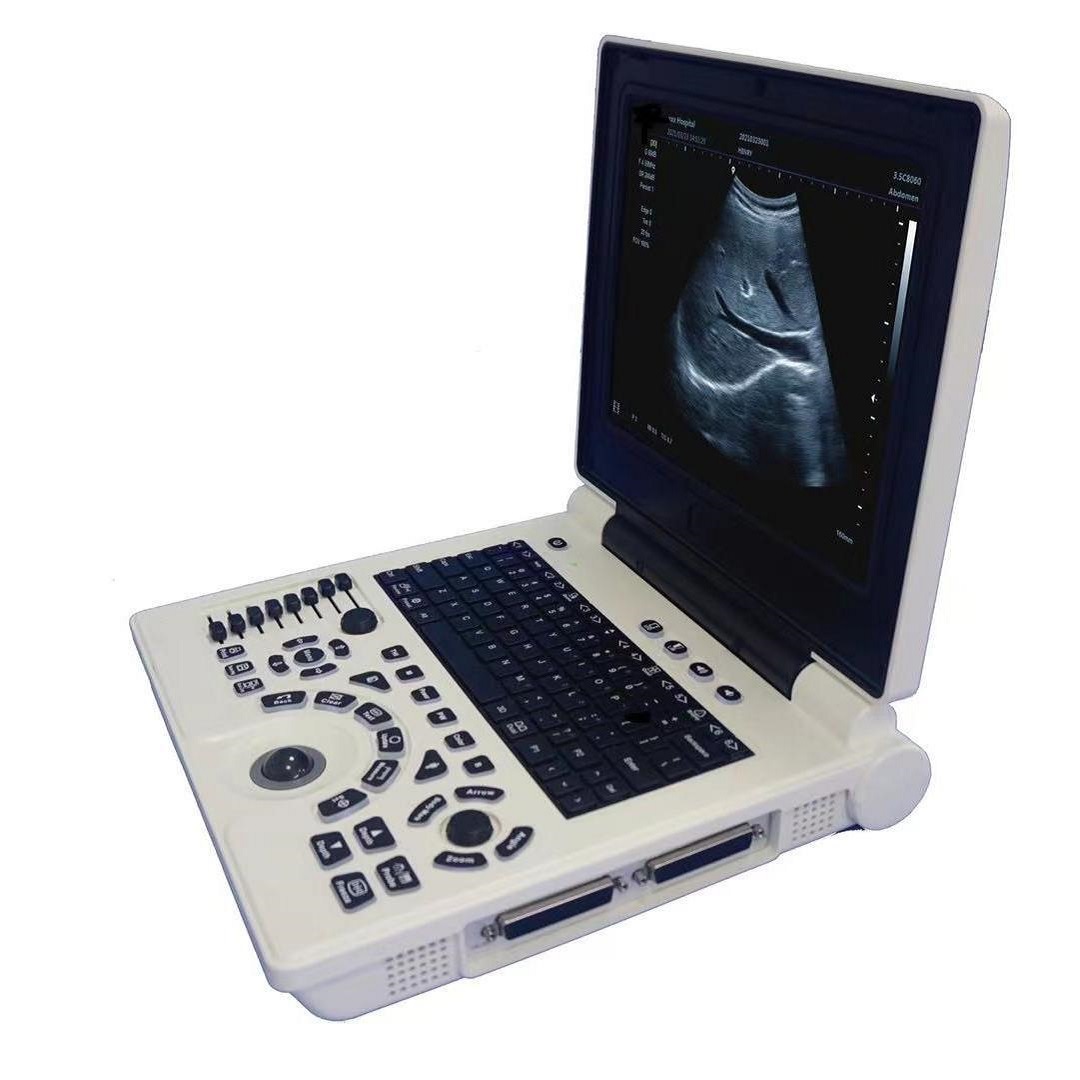

Портативный ветеринарный ультразвуковой диагностический прибор с высокой четкостью изображения, трансграничная английская версия, ультразвуковая диагностика животных

Портативный ультразвуковой аппарат Animal B; Выпуклый массивный зонд; Линейный зонд; Слегка выпуклый зонд; ректальный зонд